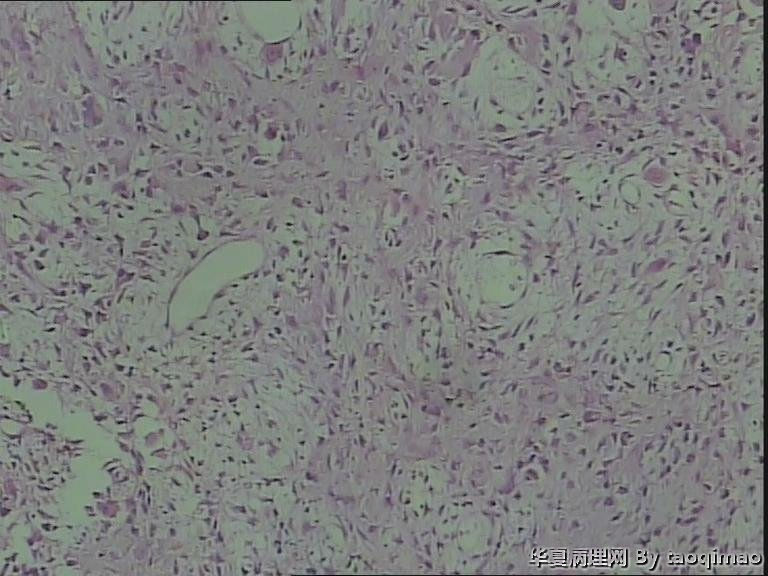

• 肋骨肿物,求助图2

图2

这是一部分容易取下来的肿瘤,其余部分还在脱钙中

患者女,31岁,胸部CT第八肋骨肿瘤,肿物在肋骨内突出骨外膜,大小2.3X1.5.切面灰白质韧

骨母细胞瘤。矿化不均要除外骨母细胞型骨肉瘤,虽然肿块小了点。还是找找核分裂,看看X线的好。